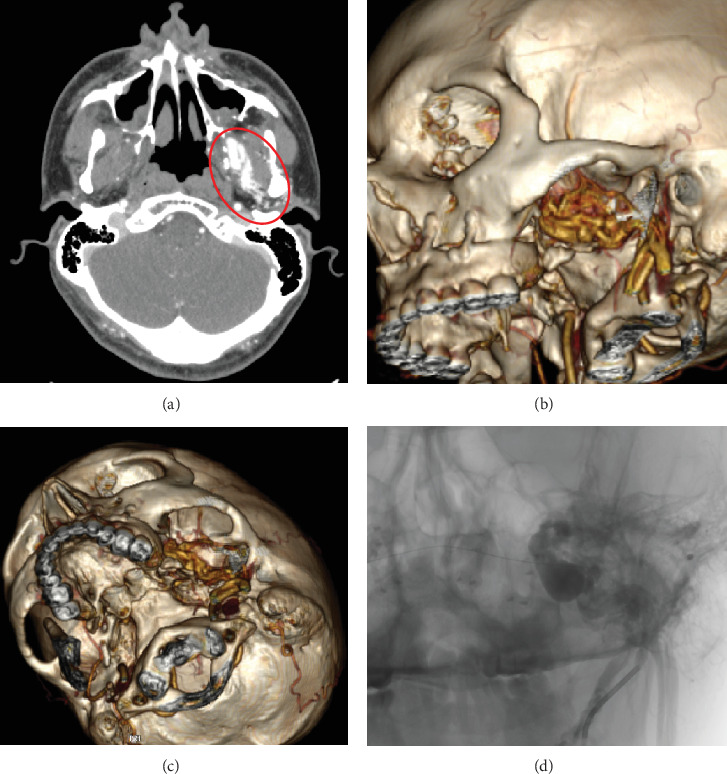

Arteriovenous fistulas rarely occur in the head and neck region. They typically arise from blunt or penetrating trauma but can develop as an uncommon complication following bimaxillary orthognathic surgery, a procedure to correct jaw deformities. This report describes a male patient who experienced an arteriovenous fistula after orthognathic surgery. We detail the diagnosis through patient symptoms and imaging, along with successful treatment via endovascular embolization. We also follow the patient for 1 year. This case highlights the importance of recognizing this rare complication to ensure prompt diagnosis and intervention. We discuss key points for preventing, diagnosing, and effectively treating arteriovenous fistulas after orthognathic surgery.